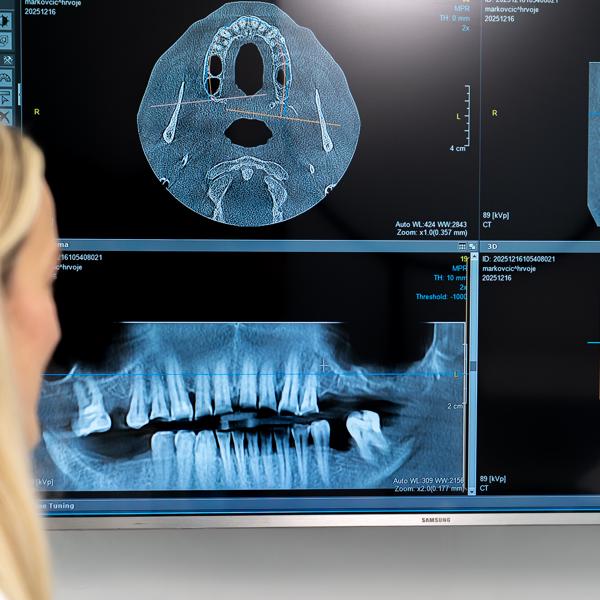

Gli impianti zigomatici rappresentano una soluzione avanzata per la sostituzione dei denti nei pazienti con una significativa perdita di osso nella mascella superiore. Si tratta di impianti speciali, più lunghi, che vengono inseriti nell’osso zigomatico, dove svolgono la funzione della radice dentale e fungono da base stabile per riabilitazioni protesiche fisse come i ponti.

Grazie alla loro biocompatibilità, si integrano in modo sicuro con l’osso e garantiscono stabilità, un aspetto naturale e una normale funzionalità durante la masticazione e il parlare. La terapia viene pianificata in modo personalizzato, sulla base di una diagnostica approfondita, e in molti casi consente di evitare interventi di rigenerazione ossea.

L’inserimento degli impianti zigomatici è considerato un intervento altamente efficace, soprattutto nei pazienti con una carenza di osso nella mascella superiore. I risultati a lungo termine sono molto elevati e il successo dipende da una corretta pianificazione, dall’esperienza del medico, dall’igiene orale e dal rispetto delle indicazioni post-operatorie.